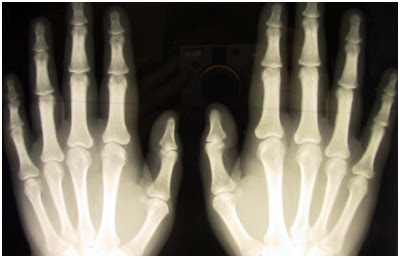

Üniversitenin bünyesindeki araştırmacılar çeşitli istenmeyen kazalar sonucu ellerinin işlevlerinde eksilmeler olan kişilere yardım etmeyi amaçlıyor.

Bu doğrultuda özellikle ellerde yer alan tendonlara bir makara sistemi kuruluyor.

Bu sayede sinir ve kas sistemleri zarar görmüş parmakların yeniden işlev kazanması sağlanabiliyor.